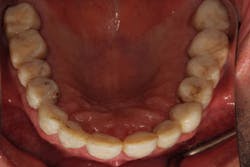

CHRIS CAME TO MY OFFICE IN AUGUST 2013, after another dental professional told him that he needed dentures. He realized that his teeth were wearing away, and he did not want to lose any more tooth structure (figure 1).

Figure 1: Before